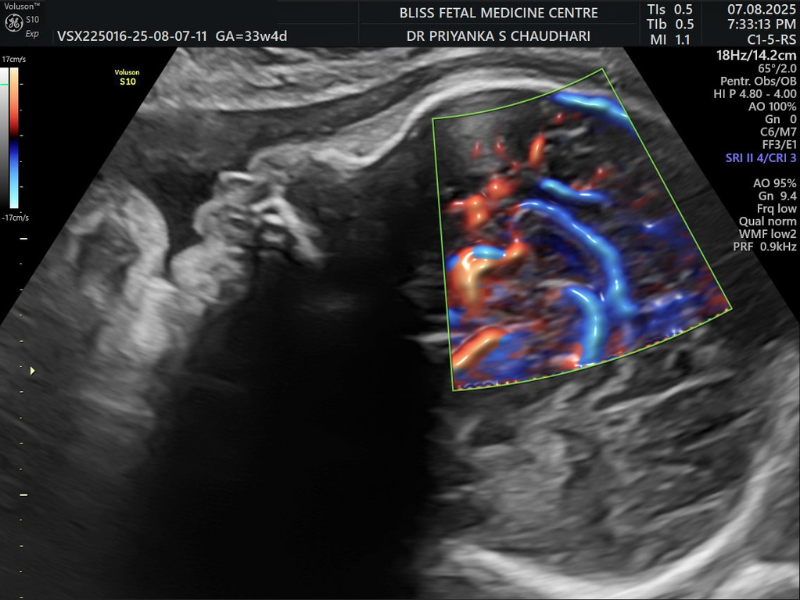

8. Fetal Colour Doppler + Biophysical Profile

Unlike standard Doppler scans, Fetal Colour Doppler converts sound waves into colour images to provide a clearer view of blood flow in the placenta and uterus. On the other hand, the Biophysical Profile (BPP) helps assess the health of the fetus via fetal heart rate monitoring and ultrasound.

When Is It Performed?

- It is performed between 28 and 32 weeks in the third trimester.

- It is needed to assess the blood flow, heartbeat and overall well-being of the baby.

- It is also needed to monitor uneven growth patterns in twins or multiple fetuses.